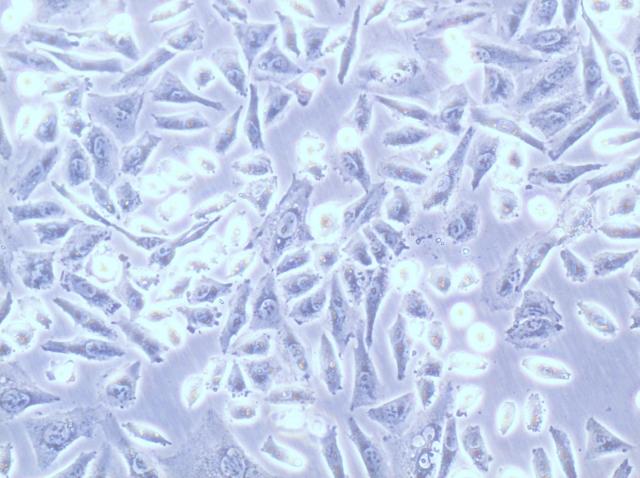

人肺癌细胞NCI-H1299

SW-620人结肠腺癌细胞

人结肠癌细胞SW-480

TE 353.Sk人正常皮肤细胞

人皮肤基底细胞癌TE 354.T

Hs 578Bst人乳腺成纤维细胞

人乳腺成纤维细胞Hs 578T

PA-1人卵巢畸胎瘤细胞

人视网膜母细胞瘤WERI-Rb-1

PLC/PRF/5人肝癌细胞

Hep-3B人肝癌细胞

人肝癌细胞SNU-398

Cates-1B人睾丸淋巴胚胎性癌细胞

人软组织纤维瘤细胞TE 115.T

HT-29人结肠癌细胞

ES-2人卵巢透明细胞癌细胞

人骨髓样甲状腺癌细胞TT

人淋巴样Burkitt淋巴瘤细胞EB-3

SW-1088人脑星型胶质瘤细胞

人前列腺癌细胞PC-3